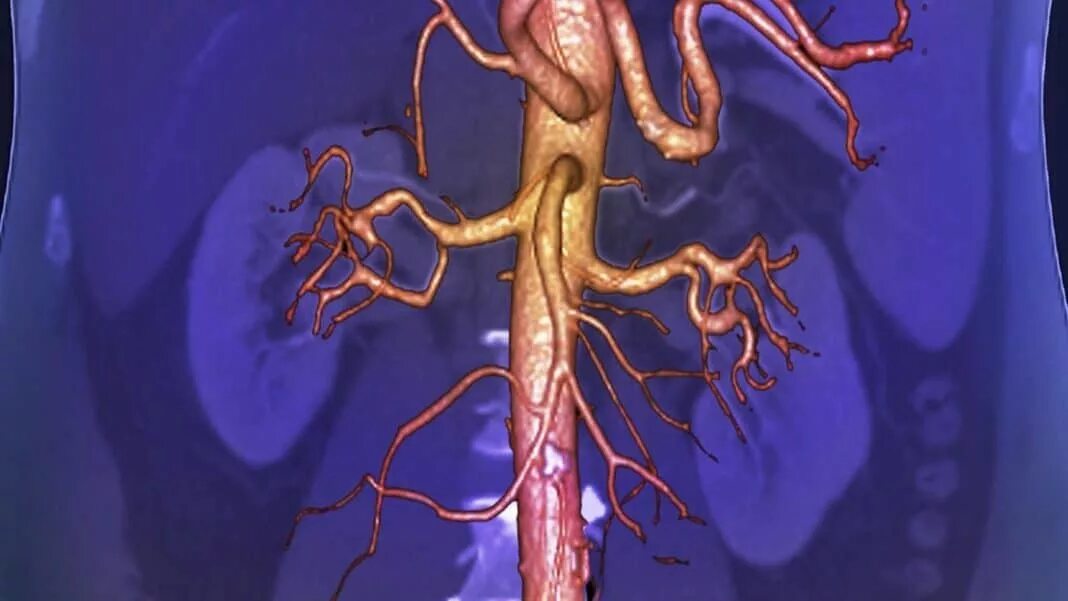

Тромбоз аневризмы аорты